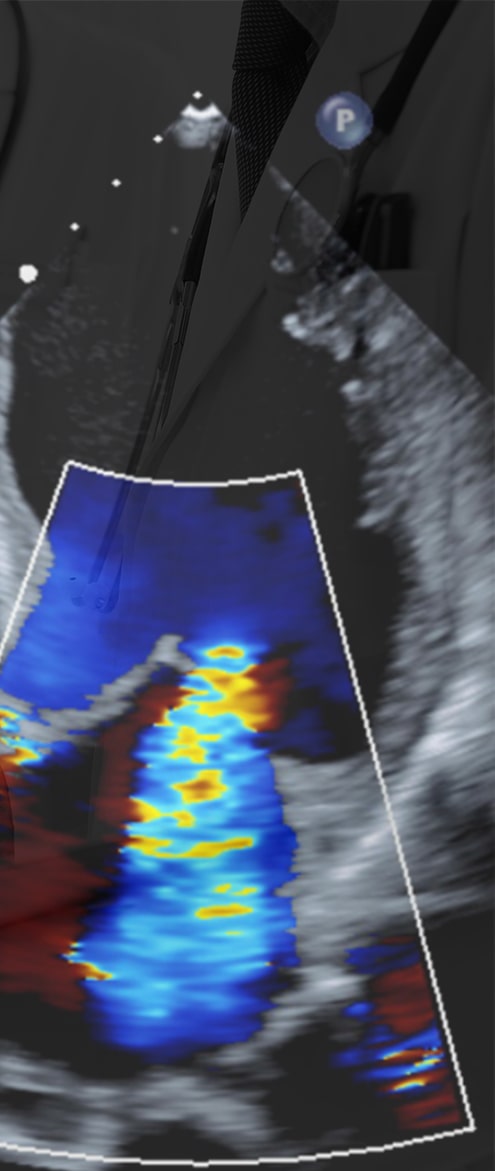

4. 当院の心エコー機械

入院施設、及び外来施設を併せて、心エコー機を計10台所有しています。最近ではEPIQ 7C(Philips社)という心エコー機に最新の経食道心エコー検査用プローブであるX8-2t(Philips社)を導入し、リアルタイム性に優れた明瞭な3次元イメージを活用しながら、構造的心疾患の診断、及び最先端の心臓弁膜症カテーテル治療に役立てています。

機械(EPIQ)

プローブ(X8-2t)

3Dイメージ